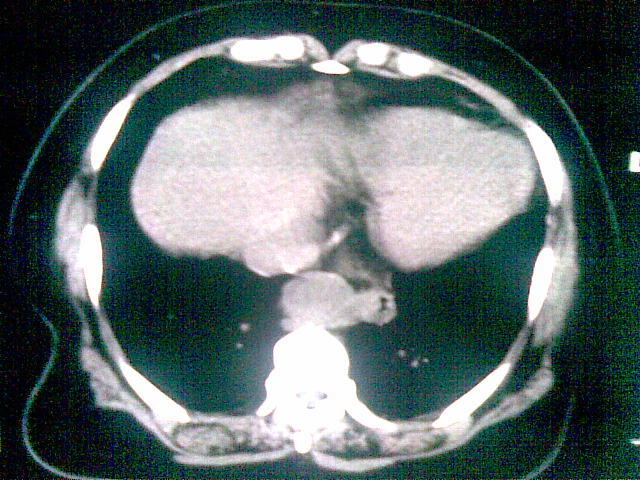

女 ,74岁,主诉食欲减退!上腹部痛,心慌!食管病变!请教ct会诊!

食道癌,心影增大